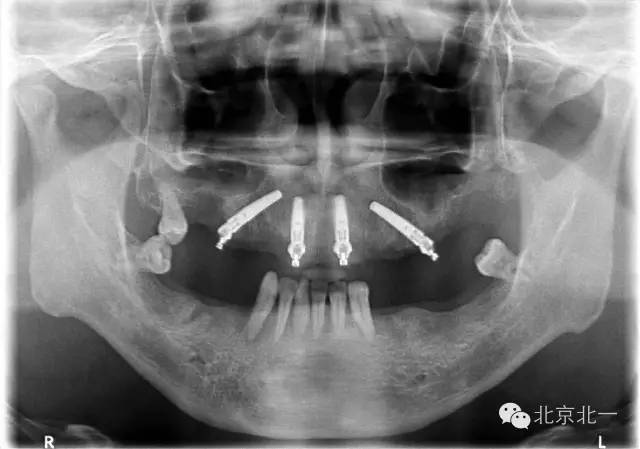

圖三、四:術(shù)中植入四枚植體,長度15mm。角度復(fù)合基臺